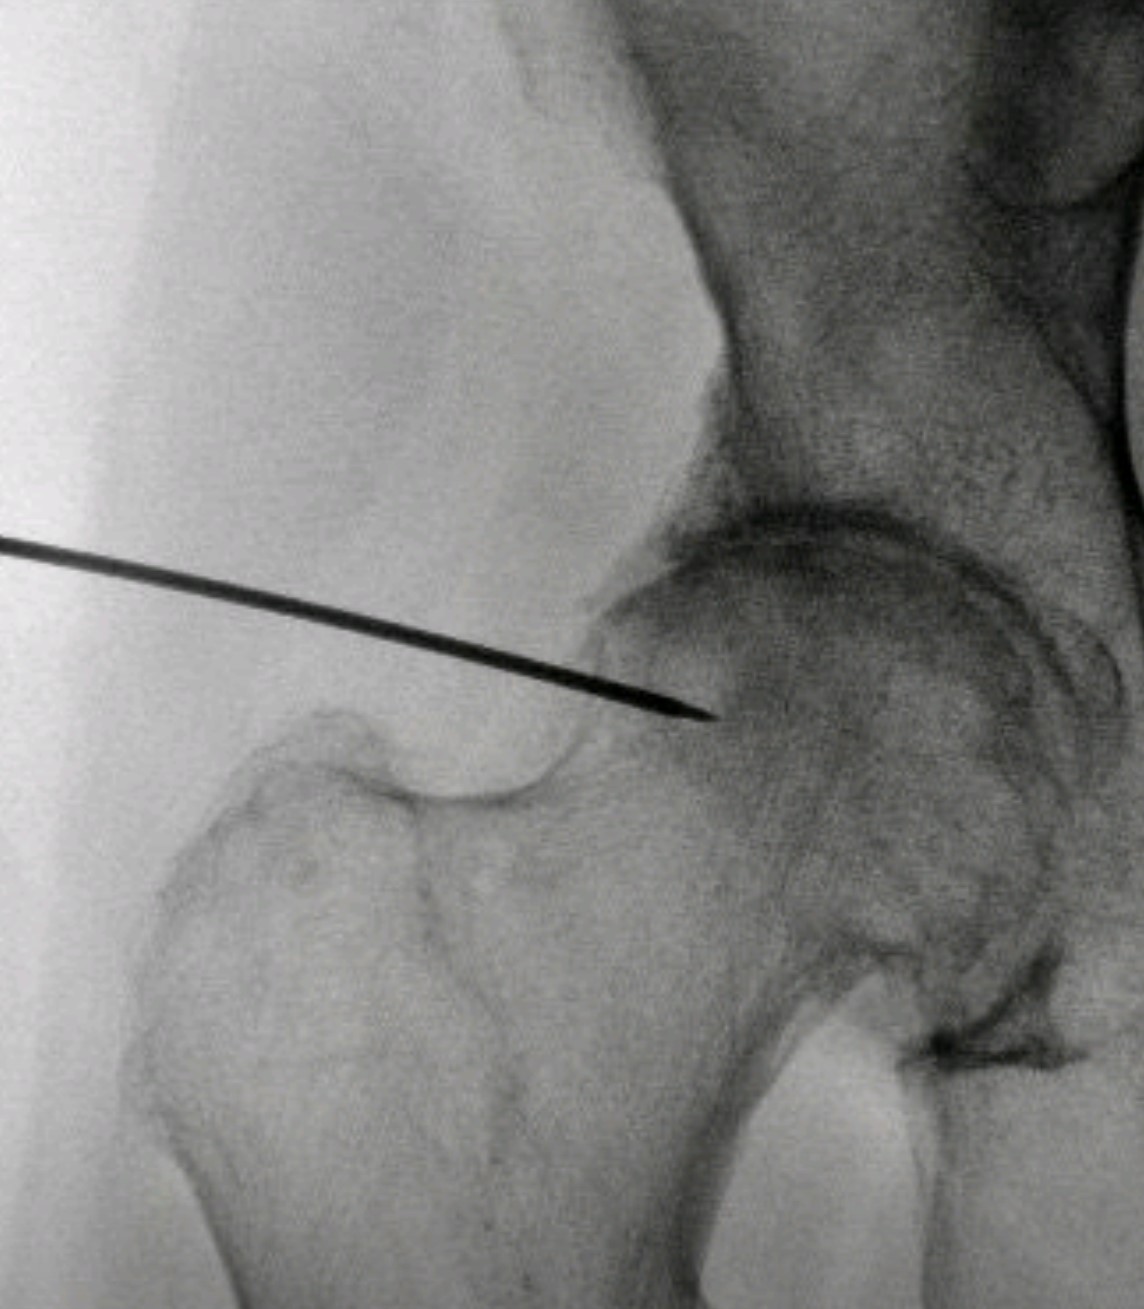

- Σε αρχικά και μέσα στάδια, η νόσος μπορεί να αντιμετωπισθεί με φαρμακοθεραπεία, εγχύσεις κορτιζόνης και υαλουρονικού στην άρθρωση υπό υπερηχογραφική ή ακτινοσκοπική καθοδήγηση και φυσικοθεραπεία.